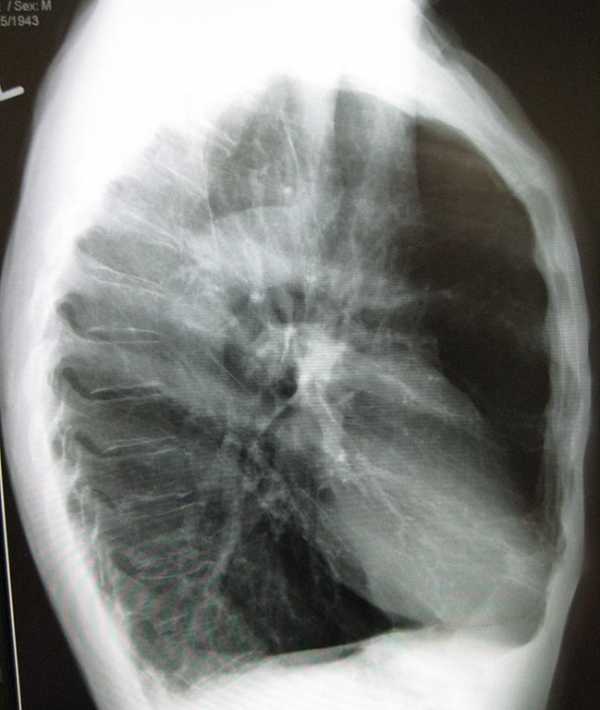

Среди симптомов эмфиземы следует отметить снижение веса, сутулость, выпячивание ямочек, которые находятся над ключицами, проблемы с прослушиванием дыхания, бочкообразную форму груди, сильную одышку. Если речь идет о развитии диффузной эмфиземы легких у взрослых (лечение ее довольно сложное), то на рентгене можно заметить, что диафрагма расположена слишком низко, а зона легких чересчур прозрачная. Сердце меняет свое положение, оно становится более вертикальным, а также возникает сильная дыхательная недостаточность. Симптоматика локализованной эмфиземы связано с тем, что травмированные участки легких давят на здоровые, поэтому у человека могут возникать даже приступы удушья.

Проводится сбор жалоб, анамнеза заболевания и анамнеза жизни пациента. Выполняется общий осмотр, прослушивание легких, общий анализ крови, рентгенография органов грудной клетки как один из ключевых методов диагностирования патологических изменений в легких. Проводится также компьютерная томография органов грудной клетки, спирометрия, исследование газового состава крови. Необходима консультация пульмонолога.

Рентген легких имеет большое значение при диагностике заболевания. У пациента с эмфиземой он покажет расширенные полости в различных отделах легких.